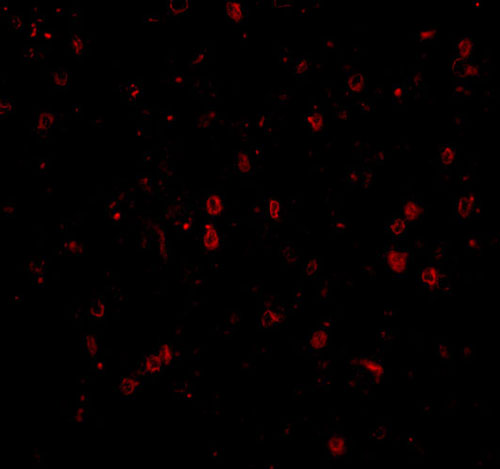

Immunofluorescence of NPAS3 in human brain tissue with NPAS3 antibody at 20 μg/mL. |